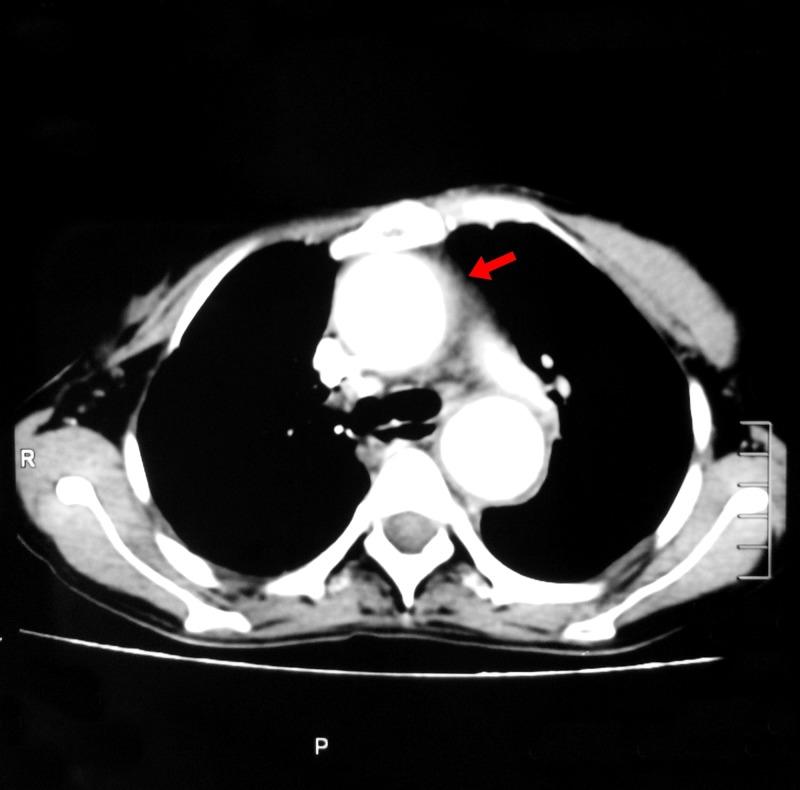

Takayasu arteritis (TA) is a chronic inflammatory large-vessel vasculitis of the aorta and its major branches. It is a relatively rare disease, which presents with a wide spectrum of clinical features. Back pain is, however, rarely described to be a presenting symptom of TA. We report a case of a 28-year-old female with no known co-morbidity, who presented with back pain along with intermittent fever, dry cough, and significant weight loss. After an extensive inpatient workup, a computed tomography (CT) scan with contrast of chest and abdomen revealed evidence of vasculitis involving aorta, common carotid arteries, renal arteries, common iliac arteries as well as external and internal iliac arteries. A confirmatory CT abdominal aortography established the diagnosis of TA. The patient was treated with long-term oral corticosteroid therapy. Our case highlights that while assessing nonspecific back pain with elevated inflammatory parameters, particularly in young women, TA should be considered as one of the differential diagnoses.

高安动脉炎(TA)是一种累及主动脉及其主要分支的慢性炎症性大血管血管炎。它是一种相对罕见的疾病,临床表现多样。然而,背痛很少被描述为TA的首发症状。我们报告一例28岁女性,无已知合并症,以背痛伴间歇性发热、干咳和显著体重减轻就诊。经过全面的住院检查,胸部和腹部增强计算机断层扫描(CT)显示有血管炎累及主动脉、颈总动脉、肾动脉、髂总动脉以及髂内外动脉。腹部主动脉CT血管造影确诊为TA。该患者接受了长期口服糖皮质激素治疗。我们的病例强调,在评估伴有炎症指标升高的非特异性背痛时,尤其是在年轻女性中,应将TA列为鉴别诊断之一。